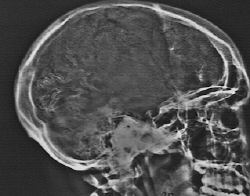

Refer to the above picture for question 4

4. The following are associated features: